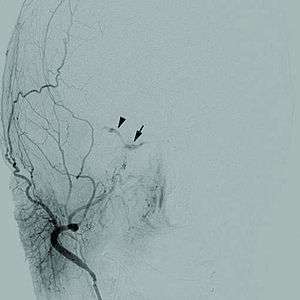

This is based on MRI scan, magnetic resonance angiography and CT scan. A cerebral digital subtraction angiography (DSA) enhances visualization of the fistula.

- Selective arteriography is used to evaluate arteriovenous fistulas.